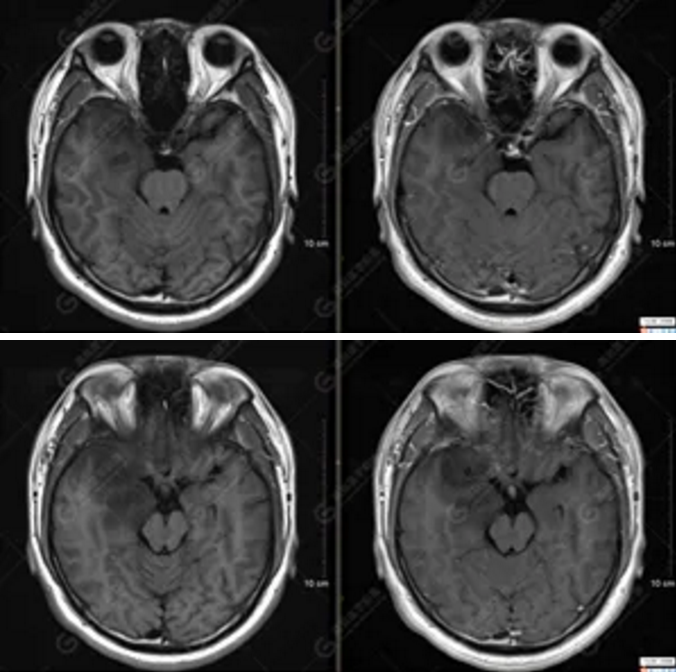

MR影像圖

【MRI平掃及增強(qiáng)檢查所見(jiàn)】右側(cè)額顳島葉、右側(cè)海馬及右側(cè)基底節(jié)區(qū)見(jiàn)一團(tuán)塊狀異常信號(hào)影,累及右側(cè)下丘腦及視交叉,大小約5.1cm×4.5cm×4.3cm,呈長(zhǎng)T1長(zhǎng)T2信號(hào),F(xiàn)LAIR序列呈等、稍高信號(hào),DWI序列呈稍高信號(hào),ADC圖高信號(hào),增強(qiáng)后無(wú)明顯強(qiáng)化;病灶周?chē)?jiàn)片狀長(zhǎng)T1長(zhǎng)T2水腫信號(hào)影,F(xiàn)LAIR序列呈高信號(hào),病灶內(nèi)見(jiàn)右側(cè)大腦中動(dòng)脈穿行。余腦實(shí)質(zhì)內(nèi)未見(jiàn)局灶性信號(hào)異常,增強(qiáng)后未見(jiàn)異常強(qiáng)化。右側(cè)側(cè)腦室輕度受壓,余腦室、腦池大小、形態(tài)均正常,中線(xiàn)結(jié)構(gòu)居中